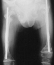

A 14-years-old boy. Body height 124 cm. Sillence type sporadic.

The first visit was at 2 years-old. He sustained one fracture

in U/E and 8 fractures in L/E, underwent 10 operations, and has

60 degrees scoliosis. He became able to walk on crutches at 2

years old and had been a practical ambulator until 12 years old.

He sustained a fracture at the distal end of right femur where

an intramedullaly nail did not reached. He uses a wheelchair for

long distant transportation. This case is supposed to be on the

border line between ambulator and non-ambulator. The diameter

of the femur was 10 mm at 3 years of age and 11mm at 13 years of age.

increase of diameter has been observed despite rather thin intramedullaly

nailing.